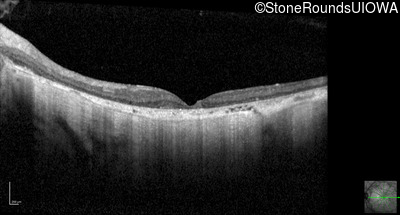

Optical Coherence Tomography - Right - 10/200

Exemplar / OCT Stack

OCT Stack